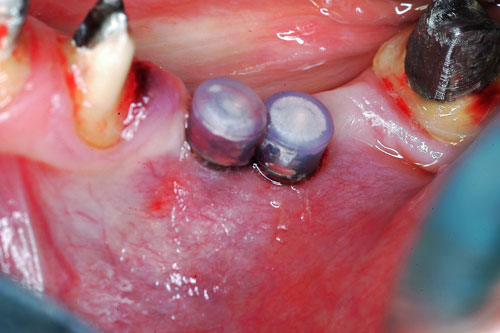

Mientras dichos movimientos ortopédicos se producen (período que supondrá otros seis meses), estudiamos los actos quirúrgicos a realizar en los cuatro implantes que pondremos. De acuerdo al estudio Desatascan realizado observamos tres situaciones diferentes: 1º-El Primer Molar Inferior Izquierdo, lo instalamos mediante Cirugía Minimamente Invasiva , con la aplicación de una Férula Quirúrgica Obtenida de los datos del scanner tratados con un programa de CMI (Cirugía Minimamente Invasiva), previa prueba en un modelo estereolitográfico, ya que la altura ósea era apenas de 9 mm. 2º- El Primer Molar Superior Derecho, se implantará mediante una ligera Elevación Atraumática (Trans alveolar) de Seno una vez logrado el espacio mesio distal necesario. 3º- El Incisivo Central Superior Derecho ausente, cuenta con un sustrato óseo prácticamente inexistente. El espesor de la tabla era de menos de 2 mm. Los caminos posibles a seguir para contar con una Rehabilitación de piezas independientes son dos: Optamos por esta segunda opción por ser menos cruenta y no necesitar de una zona dadora. Técnica esta que pondremos en práctica en dos etapas diferidas: 1º-Incisión horizontal palatinizada, incisiones peri rodetes gingivales e incisiones de descarga. Dilatación que comenzamos con dos incisiones de descarga sobre la cortical vestibular realizadas con disco. y el comienzo de la dilatación propiamente dicha mediante una hoja de bisturí, para luego seguir con un periostótomo . Recién después de alcanzada una cierta separación de la cortical vestibular de la palatina, empezamos con los dilatadores roscados. En este punto podríamos haber utilizado sin riesgos un Implante de 3,8 mm de diámetro, pero a fin de mejorar la estética del pilar emergente decidimos rellenar con material osteoconductor y osteoinductor (BiOss) y cubrir mediante membrana reabsorvible ( Bio Guide). 2º-Implantación seis meses después. Mientras se van cumpliendo los tiempos antes mencionados, y comprobamos reiteradamente la funcionalidad de la oclusión con los provisorios, tomamos impresiones definitivas y construimos primero el maxilar inferior, para definir en primer término la porción inferior de la Guía Anterior., y a nivel posterior Curvas y Microplanos. Para luego realizar los cuadrantes premolar- molar del superior: La espera de la regeneración ósea y sus tiempos pertinentes, más la espera de los tiempos de la implantación, nos obligaron a modificar las etapas del protocolo D.AT.O de manera de mantener la –D- mediante el sector superior de la GA. en provisorios, mientras fuimos resolviendo en forma definitiva los demás sectores. Ya pasados los meses necesarios para recrear un hueso adecuado en el área del Incisivo Superior Derecho, procedemos a resolver la implantación de dicha zona, observando que todo el esfuerzo dedicado al mismo había sido inútil, ya que la formación de hueso se produjo minimamente. Cuatro meses después tomamos impresiones del sector Antero Superior de la Guía Anterior, incluyendo el arrastre de un transfer . Seguimos modelando la encía con un nuevo juego de provisorios. Y se construye entonces el sector superior de la Guía Anterior. Se efectúa un control radiográfico a los 6 meses. Se ha intentado mostrar en esta Rehabilitación, que a pesar de las distintas circunstancias de cada paciente, siempre debemos tener en cuenta la necesidad de ejercer la DESOCLUSIÓN del caso como prioridad número uno, para luego perseguir la ALINEACIÓN TRIDIMENSIONAL de las arcadas y obtener así una OCLUSIÓN equilibrada. D.AT.O. ES EL PROTOCOLO QUE DEBEMOS SEGUIR EN TODA REHABILITACIÓN. BIBLIOGRAFÍA 1)William Mc Horris,B.S.,D.D.S. Oclusión. Con especial énfasis sobre :El rol funcional y parafuncional de los dientes anteriores. 2)Von Spee , Craff(Anatomista alemán, describió la curva de compensación de la articulación de molares y premolares).CURVA DE SPEE 1.89 3)Stuart,D.”Some aspects of the inervation teeth.”Procedings of Royal Society of Medicine.20:1675,19274)Muhleman,H. y Savdir,S”Tooth movility-its causes and significance”Journal of Periodontology ,36:153,Marzo ,Abril,1965. 4)Muhleman,H. Y Savdir,S”Toothmovility its causes and significance” Journal of Periodontology,36:153,marzo,abril,1965. 5-Oclusión y Diagnóstico en Rehabilitación Oral. 6-Anatomia Odontológica. 7-A contribution to the study of the movementes of the mandible. 8-Celenza F.W, Nadeskin J.F.,Oclusión.Situación actual. 9-D´Amico 10-Dawson P.E. 11-Huffman –Regenos. 12-Hobo S.-Takayama H.A. 13-Lucia V.O 14-Mc Horris. 15-Mc Horris. 16-Stuart C. 17-Vartan Veshnilian 18-Alvarez Cantoni H. AUTOR:Ratificación del Protocolo en Rehabilitación Bucal a pesar de las incidencias propias de cada caso clínico. A propósito de un caso.

Se utilizarán dos Implantes roscados de 8 mm de longitud por 3,8 mm de ancho.

Los implantes correspondientes a la pieza 36 (dos implantes cortos), fueron realizados con CMI(cirugía minimamente invasiva), técnica que preferí ya que dejando el tejido conectivo fibroso DEL LADO LINGUAL….que es el que la paciente tenía mas dificultades por ejercer fisioterápia de cepillo, estría mucho mas protegido de posibles periimplantitis futuras ya que el lado vestibular no tenia dificultades manuales para cepillar.